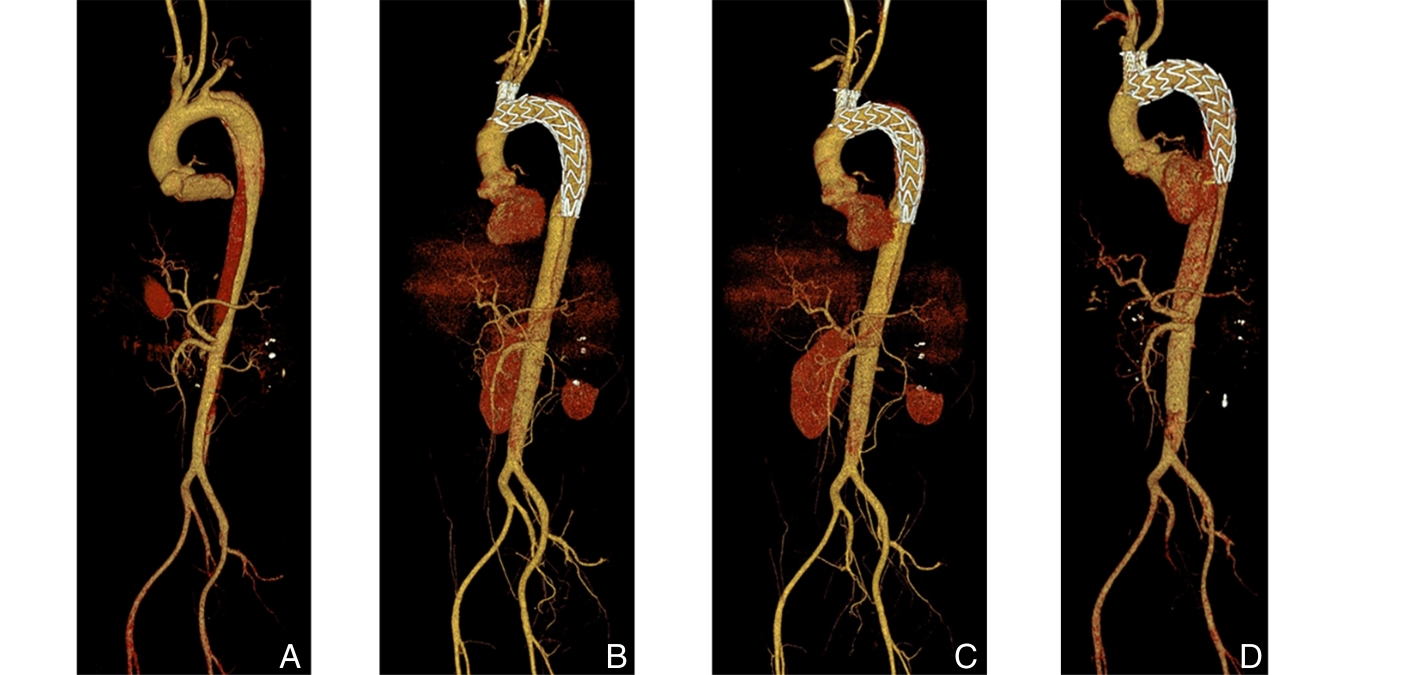

- 腹主动脉瘤腔内修复术中纤维蛋白粘合剂瘤腔填充技术专家共识

2026,35(2):201-222, DOI: 10.7659/j.issn.1005-6947.250652